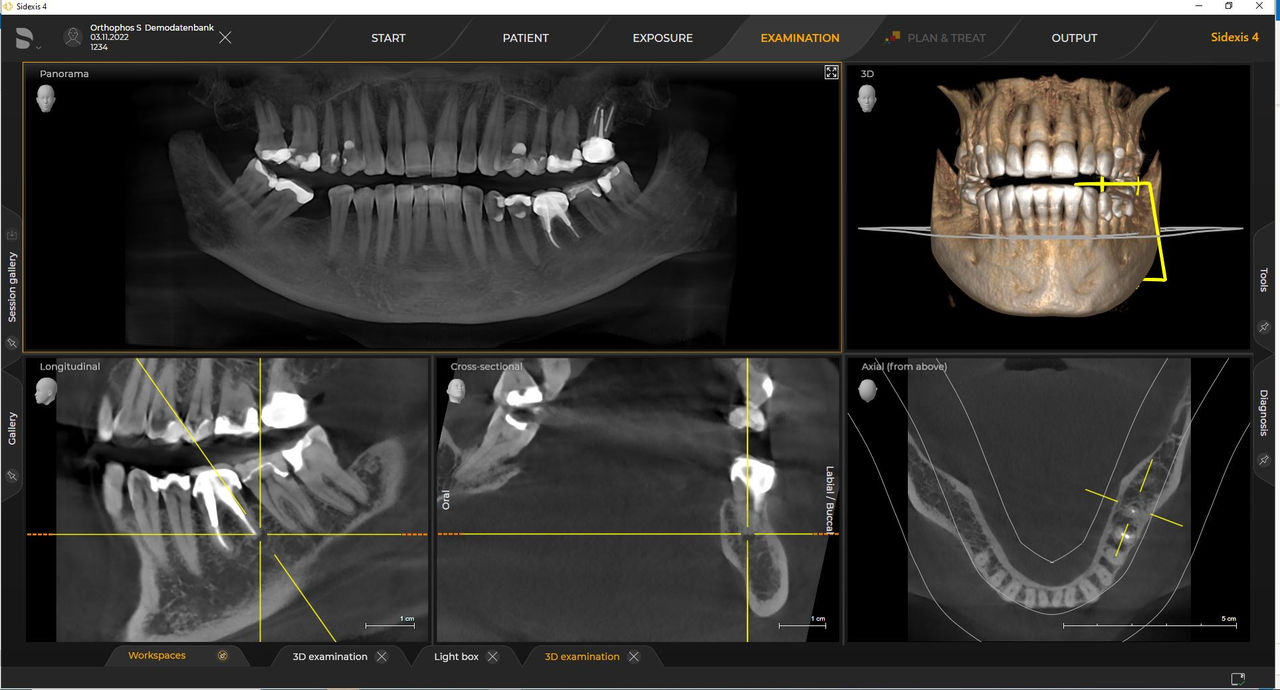

Wytyczne te są zgodne z wymaganiami oprogramowania do przetwarzania obrazu Sidexis 4 i Orthophos S. Więcej informacji można znaleźć w wymaganiach systemowych rozwiązania Sidexis 4 i instalacyjnych systemu Orthophos S.

Urządzenia rentgenowskie firmy Dentsply Sirona współpracują wyłącznie z systemem Sidexis 4. Można łatwo przenieść dane z systemu Sidexis XG do systemu Sidexis 4. Sidexis 4 zapewnia pełną funkcjonalność cyfrową dzięki najnowszym narzędziom